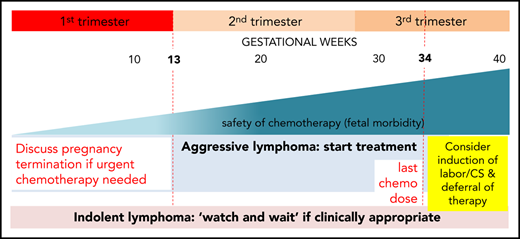

Optimal time to initiate therapy

Administration of chemotherapy while the woman is pregnant, thus exposing her infant to potential complications with these agents, must be balanced with the very real risks associated with prematurity. It is accepted that the chemotherapy agents will cause neutropenia and immune suppression in the fetus, and it is recommended that delivery is delayed for 3 weeks after administration of chemotherapy to avoid birth when the infant will be immunocompromised. In practice, this generally means that, for most women, chemotherapy would not be given after 34 weeks gestation. It is important to discuss a woman’s preferences for birth and review her prior obstetric history especially a history of preterm birth.

In the case described, we favor planning of birth as soon as it is safe to do so with minimal risks to the fetus and mother. Full diagnosis and staging were complete by 33 weeks of gestation. Giving the first cycle of chemotherapy would have the benefit of reducing the size of the large mediastinal mass and relieving the SVC and airway obstruction. This would make the birth safer for the woman and gain fetal maturity with limited exposure to immunochemotherapy. Birth after 36 weeks of gestation carries a low risk of complications of prematurity, and timing of administration of chemotherapy to plan for birth after this gestation should be the goal.

Because PMBCL is relatively rare and a recently described distinct clinicopathologic entity by the World Health Organization Classification, there are few prospective studies and no randomized prospective trials to inform on what the optimal approach should be. Although once considered to be a subset of diffuse large B-cell lymphoma (DLBCL), the disease is clinically and molecularly very different from other types of DLBCL.11 In fact, its clinical and biologic characteristics resemble classical Hodgkin lymphoma (cHL) much more closely.12,13 Early studies in the disease, albeit retrospective comparisons, suggested that regimens with higher-dose intensity than cyclophosphamide, doxorubicin, vincristine, and prednisone (CHOP) were associated with improved survival, and hence these have been developed for PMBCL. The important role of dose intensity is not surprising given the close biologic relationship of PMBCL to cHL, where higher dose intensity is beneficial in certain high-risk patients. One single-center prospective study and a large multicenter retrospective study demonstrated high efficacy that obviated the need for radiation therapy with the dose-adjusted etoposide, prednisone, vincristine, cyclophosphamide, etoposide, and rituximab (DA-EPOCH-R) regimen.14,15 Recognizing that there has not been a direct comparison in PMBCL specifically of DA-EPOCH-R and rituximab + CHOP (R-CHOP; the standard regimen in DLBCL) but high single-arm efficacy with the former regimen, we would favor instituting DA-EPOCH-R for PMBCL in the third trimester. Etoposide as is the case with most of the other drugs has not been well studied in pregnancy, but limited retrospective experience with it, particularly in the third trimester, suggests that it is safe. Other approaches that are more intensive than R-CHOP such as rituximab + doxorubicin, cyclophosphamide, vindesine, bleomycin, and prednisone (R-ACVBP) have been used successfully in young nonpregnant patients, but to our knowledge, there are little retrospective data on their use in pregnancy. The decision on which regimen to use is more challenging in the earlier trimesters as discussed in the context of case 2. Localized radiation treatment is used extremely rarely in the management of SVC syndrome in the context of lymphoma given its sensitivity to steroids and chemotherapy; we would recommend their use once the diagnosis is made. For most patients presenting with DLBCL in pregnancy, we recommend R-CHOP therapy.16 In a nongestational setting, high-grade B-cell lymphoma with chromosomal rearrangements of MYC and BCL2 and/or BCL6 are rarely encountered in younger patients and may benefit from an alternative approach. This should be no different in the setting of pregnancy.

The patient initially received high-dose steroids for treatment of her SVC syndrome once the diagnosis was made. She then received her first cycle of DA-EPOCH-R therapy at 33+3 weeks of gestation and tolerated it very well. Additionally, growth colony-stimulating factor was administered with no complications. An MRI of the chest was performed 2 weeks later and showed reduction in the size of the mediastinal mass to 8.6 × 4.5 × 5.4 cm with significant improvement in SVC and airway compression. Labor was induced at 35+5 weeks, and our patient had an uncomplicated vaginal birth to a healthy girl (birth weight, 2585 g) who had no neonatal complications. She received her second cycle of DA-EPOCH-R on day 22 as per the chemotherapy regimen without complication on the fourth postpartum day and subsequently completed a total of 6 cycles of therapy. CT and FDG-PET scans were done at completion of therapy, showing significant shrinkage of the mass on CT (Figure 1C) and complete metabolic response on FDG-PET, and she did not require consolidation mediastinal radiation. She remains in complete remission at last follow-up.

Management of lymphoma in early pregnancy

Organogenesis is ongoing in the embryo until 10 weeks of gestation (8 weeks after conception), so there is higher potential for teratogenicity from medications or radiation until this period is complete. The fetal phase begins at 10 weeks of gestation until birth, with continued growth and maturation of formed organs and exposure to medications during this phase may result in growth restriction but typically not gross structural abnormalities. Some organs with potential higher vulnerability to chemotherapy include the central nervous system, hematopoietic system, and eyes, but in general, administration of chemotherapy in the second and third trimester has been considered relatively safe.17,18 However, as with other drugs, chemotherapy may affect fetal organ functionality. In 1 large published (retrospective) experience of lymphoma in pregnancy (90 women; Table 2), 11 patients were diagnosed in the first trimester, and of these, 6 pregnancies were terminated to enable immediate chemotherapy.19 In this same series, the median gestational age for women (n = 56) who received antenatal therapy was 22 weeks. Combination chemotherapy was administered to 89% of women, with 37 (66%) receiving therapy in the second trimester. Therapy was deferred in 28 (33%) women until postpartum who were diagnosed at a median of 30 weeks of gestation. There were no increased pregnancy complications such as preterm birth, preterm induction of labor, premature rupture of membranes, or preeclampsia in women who received antenatal vs deferred (postnatal) therapy. Median birth weight was similar, but there was a trend to small-for-gestational age infants in women who received antenatal chemotherapy. This data set did not identify significant increased fetal morbidity or mortality with treatment institution in the second and third trimesters.20,21 Another recent study looking at 134 pregnant women with HL identified that survival did not differ between pregnant and nonpregnant women, but preterm labor and rupture of membranes was higher in HL patients who received antenatal therapy compared with cases where it was deferred until postpartum.22 Institution of chemotherapy in the first trimester is not well studied, and outcomes are likely very dependent on the gestational time point because it is the period of major organogenesis. For patients diagnosed with HL in late first trimester (as our case) with advanced symptomatic disease, urgent therapy initiation (or with short delays to start in the second trimester) is reasonable.

Choice of treatment approach for HL

Adriamycin, bleomycin, vinblastine, and dacarbazine (ABVD) administered every 2 weeks is the most commonly used regimen in the treatment of HL during pregnancy.23 Several reports demonstrate that it can be safely administered in the second and third trimesters. For patients with advanced stage disease, alternatives such as brentuximab with AVD (omission of bleomycin) or escalated bleomycin, etoposide, doxorubicin, cyclophosphamide, vincristine, procarbazine, and prednisone may be considered for HL outside of pregnancy.24 However, these are significantly more toxic than ABVD, there is a paucity of experience using these platforms in pregnancy, and we would therefore recommend avoiding their use in pregnancy at this point in time. For novel agents such as brentuximab, there are no data regarding their use in pregnancy, and their potential teratogenic and toxic effects are unknown.25,26 In terms of duration of therapy, for early-stage favorable patients, shorter duration of ABVD may be feasible, and for advanced-stage patients who are disease negative after 2 cycles, the bleomycin in ABVD may be dropped if interim PET results are negative.27,28 There is little experience using radiation as a therapeutic modality for lymphoma during pregnancy. We discuss its use below, but in this setting, we favor avoiding its antenatal use other than in exceptional circumstances.

Other lymphomas in pregnancy

From the limited series that have looked at this, T-cell lymphomas make up a significant proportion of NHLs that occur during pregnancy. The principles of management of T-cell lymphomas diagnosed during pregnancy are the same as discussed above for our 2 cases; however, when these diseases occur in this age group, presentations are typically highly aggressive needing emergent chemotherapy, and frequently multiagent intensive regimens are necessary making the risk of complications to the mother and fetus high. This is also the case for Burkitt’s lymphoma diagnosed during pregnancy. Other rarer lymphomas that are encountered in this setting are follicular lymphoma and other indolent lymphomas such as mucosal-associated lymphoid tissue associated lymphoma: these diseases tend to have a much less aggressive presentation at diagnosis and mostly can be managed with a watch-and-wait approach. We would not recommend extensive radiologic work-up of these diseases when they are diagnosed in pregnancy, and this should be deferred (as should therapy if possible) to the postpartum period.